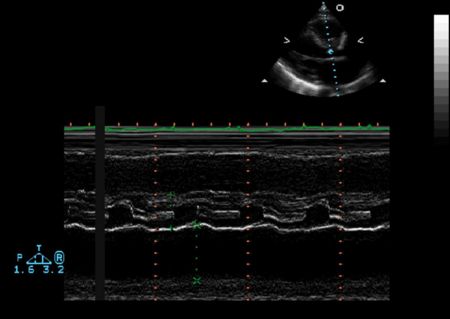

Ventricular M-mode

- Ventricular Wall Thickness

- Ventricular Chamber Size

- Intraventricular Masses

M Mode in Tamponade

- Diastolic collapse of the right ventricle